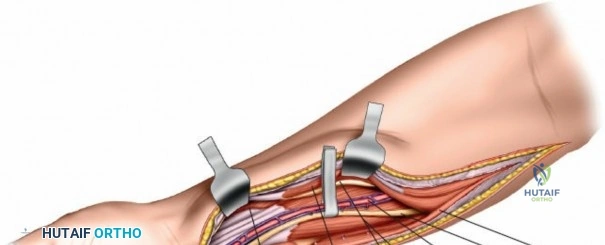

Patient Positioning and Operating Room Setup

Place the patient supine on the operating table. The affected upper extremity is extended onto a radiolucent hand table or arm board. The shoulder should be abducted to approximately 90 degrees, and the elbow extended. A pneumatic tourniquet is applied high on the brachium. The setup must allow for unimpeded use of intraoperative fluoroscopy (C-arm), which should be positioned parallel to the arm board to allow for easy anterior-posterior and lateral imaging without compromising the sterile field.

Make a straight or gently curved incision beginning at the anterior flexor crease of the elbow, just lateral to the biceps tendon. Extend this incision distally toward the styloid process of the radius. The exact length and placement of the incision are dictated by the specific pathology; the approach is highly modular, and often only the proximal, middle, or distal third of the incision is required.

Superficial Surgical Dissection and Internervous Plane

Retractor Placement and Fixation Technique

Once the proximal radius is exposed, great care must be taken with retractor placement. Never place Hohmann or levering retractors blindly around the posterior surface of the radial neck. Because the PIN may touch the bone posteriorly in up to 25% of patients, a posteriorly placed retractor can easily crush the nerve against the radial cortex. Instead, use gentle right-angle retractors or place retractors only on the anterior and lateral aspects of the bone, utilizing the elevated supinator as a shield.

For fracture fixation, a dynamic compression plate or locking compression plate is applied to the volar surface of the radius. The volar surface provides a flat, mechanically advantageous surface for plating and allows for excellent soft tissue coverage by the overlying muscle bellies upon closure. Ensure that the natural radial bow is meticulously restored during reduction to guarantee full postoperative pronation and supination.